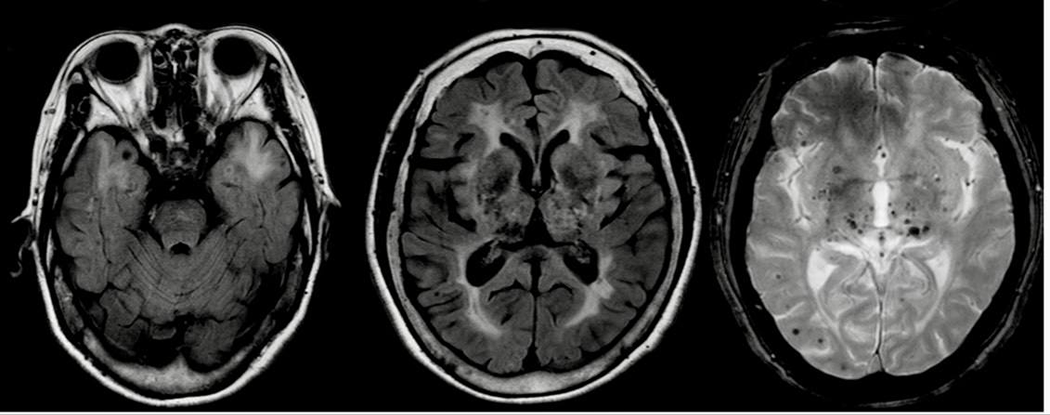

• МРТ головного мозга с контрастом: в червя мозжечка кистозное образование с узловым компонентом, накапливающим контраст, без перифокального отека; в продолговатом мозге два маленьких контрастирующих очага до 3-4 мм без масс-эффекта.

МРТ ГМ